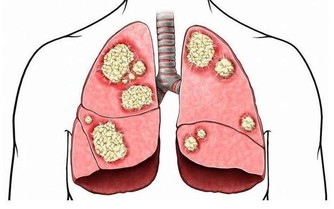

肝臟是人體最大的排毒器官,健康的肝臟可避免腹脹、便秘等麻煩,同時也起著調節血糖的重要作用。中醫常說:“養肝就是養命”,如果肝臟代謝不正常,人體所需的養分得不到及時供應,身體各個器官都無法正常工作。今天就帶著大家看看這9大隱蔽的“肝臟殺手”。

過量飲酒會降低肝臟淨化血液的能力,導致體內毒素增加,誘發肝臟損傷及多種疾病。

另外,酗酒還容易導致肝臟中毒,誘發肝炎。長期過量飲酒則容易導致肝硬化。每天飲高濃度酒超過兩杯(25 毫升)就會傷肝。